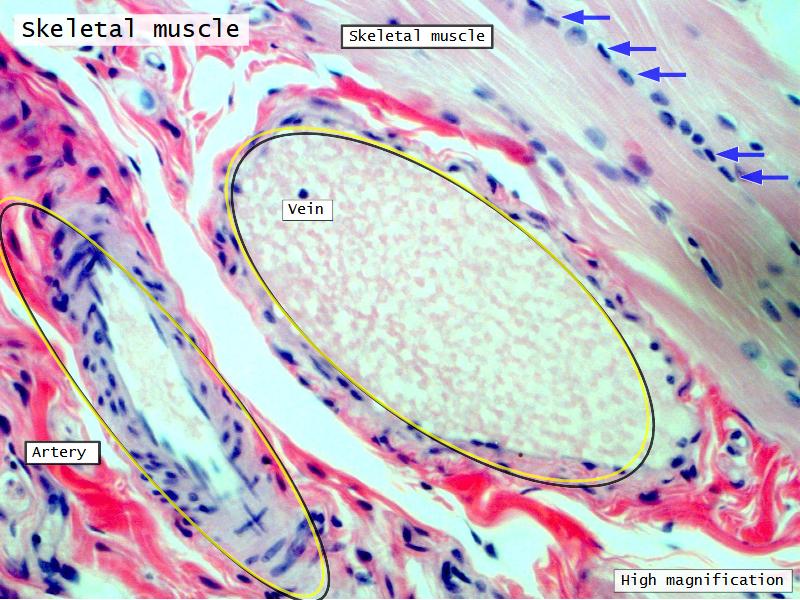

The cardiovascular system needs to be connected to the respiratory system.Path of O2 and CO2

- List complete

- With layers

- And cells

- And function of each

Components of the Blood-Air Barrier?